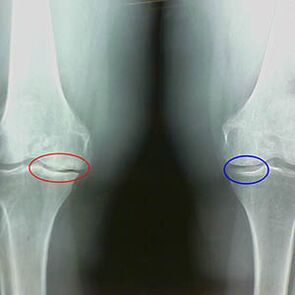

O grao de artrose está determinado por x -rayIntercambio de participación no proceso patolóxico das estruturas óseas. O seu cambio demostra que o sistema muscular tivo un desequilibrio de 5 a 10 anos. Normalmente a xenteExperimentas dor dolorosa durante varios anos.

A segunda etapa da artrose é vista como sinxela. A imaxe x -ray mostra esporas óseas significativas, pero a cartilaxe non se ve afectada. A cantidade de fluído sinovial redúcese, pero despois de longos síntomas de dor e correr, rixidez na articulación e dor ao dobrar e na posición nos xeonllos.

Características do feixe de primeiros tempos da segunda etapa da artrose do xeonllo:

- Os bordos apuntados dos tubérculos internos sobre a tibia, aos que está conectada a banda definida cruzada;

- Estreitamento da brecha común no lado medial;

- Os bordos apuntados do condilo óseo nos lados mediais, con menos frecuencia no lateral, dependendo do desenvolvemento do valgus ou da deformación da conexión variante.

Para a segunda etapa en Larsen O estreitamento da brecha común en máis dun 50% é característicoNon obstante, isto só se pode comprobar en dinámica ou en comparación cun ininterrompido das articulacións.